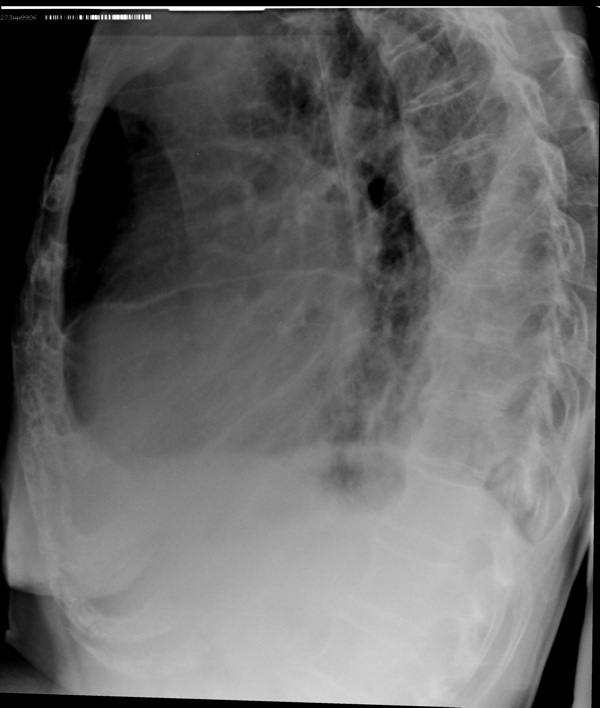

Пневмония – простыми словами воспаление легких – острое воспаление легочной ткани инфекционного происхождения с преимущественным поражением альвеол и интерстициальной ткани легкого. При этом жидкость скапливается в просвете альвеол, что ведет к уменьшению дыхательной поверхности легких. Пневмония может быть самостоятельным заболеванием или быть осложнением другого. Заподозрить пневмонию можно при аускультации (выслушивании) легких при дыхании. Поздняя диагностика и задержка с началом антибактериальной терапии ухудшают прогноз заболевания, возможен летальный исход. Поэтому при малейших подозрениях необходимо сделать рентген легких, особенно пожилым пациентам, а при подтверждении диагноза – поставить вопрос об экстренной госпитализации. Пневмония может лечиться и дома, но такое решение может принять только врач, основываясь на оценке состояния больного, рентгенологической картины легкого и анализов крови. Лечение пневмонии в большинстве случаев требует внутривенного введения антибиотиков, инфузионной терапии (капельниц) и других препаратов. Пациенты, обратившиеся в медицинский центр «Ваше Здоровье», смогут получить весь комплекс необходимых лечебно-диагностических мероприятий, в т.ч. рентген на дому.

Второй наиболее частой причиной, по которой выполняется рентген грудной клетки, является травма груди с подозрением на перелом рёбер. Может показаться, что ушиб грудной клетки является несерьезным основанием, чтобы обратиться к врачу и сделать рентген. Однако приглушая боль приёмом обезболивающих препаратов, можно пропустить ряд опасных осложнений. Сломанные рёбра могут ранить легкое и вызвать пневмоторакс, т.е. скопление воздуха, или гемопневмоторакс, т.е. скопление крови и воздуха в грудной полости. Перелом трех и более рёбер может вызвать серьёзные дыхательные нарушения, что особенно опасно у пожилых пациентов. Поэтому не стоит рисковать здоровьем и необходимо сразу обратиться к врачу. Пациенты, обратившиеся в наш медицинский центр "Ваше Здоровье", смогут получить весь комплекс необходимых лечебно-диагностических мероприятий, в т.ч. рентген на дому.